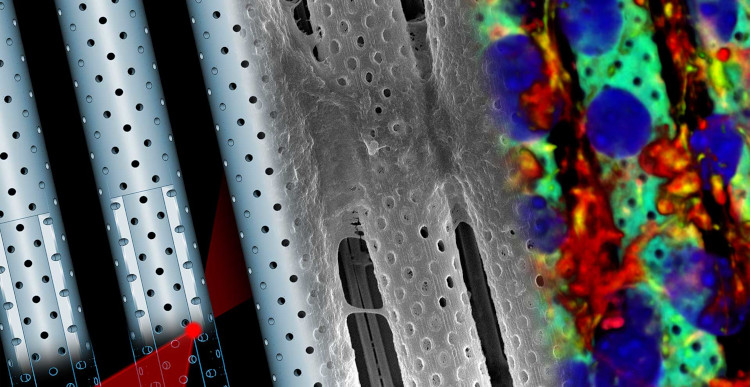

Center for Advanced Biomaterials for Health Care

Interdisciplinary Research Centre on Biomaterials (CRIB), Naples

The Center for Advanced Biomaterials for Health Care (CABHC) develops materials and technologies to engineer bio-logically inspired platforms and systems for applications in the biomedical sector.